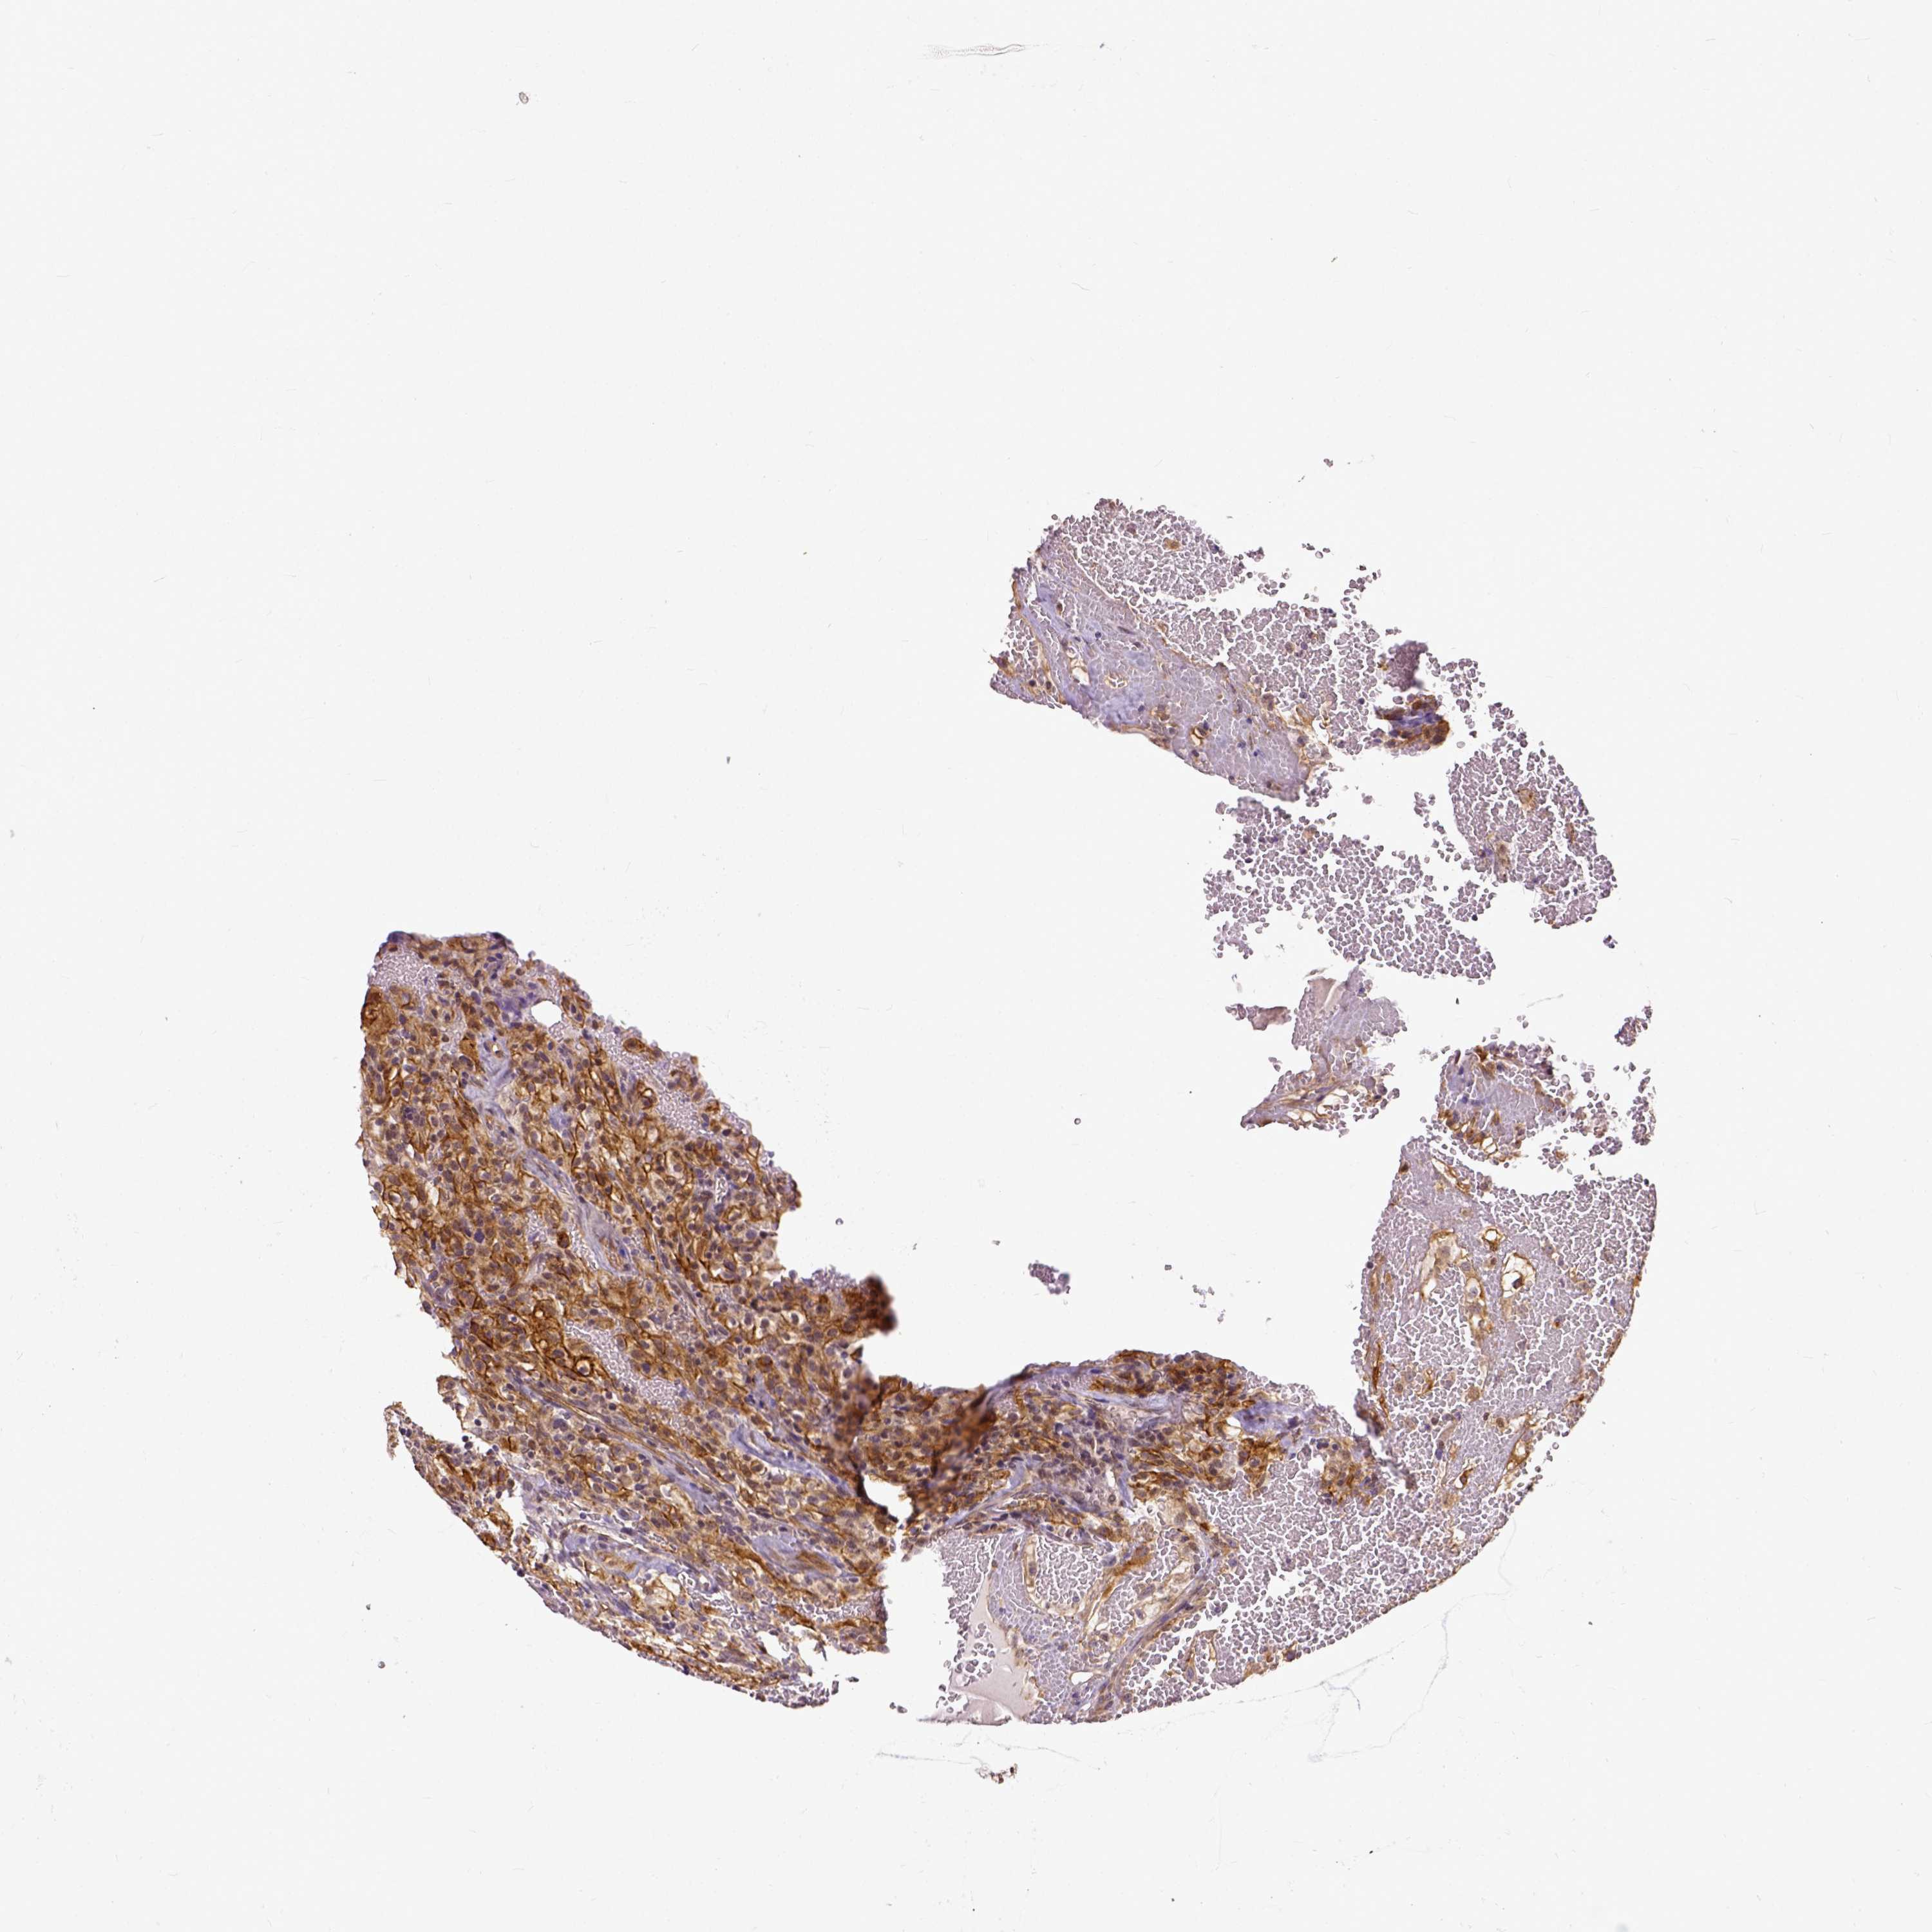

KIDNEY RENAL PAPILLARY CELL CARCINOMA (TCGA) - Interactive survival scatter ploti

The Survival Scatter plot shows the clinical status (i.e. dead or alive) for all individuals in the patient cohort, based on the same data that underlies the corresponding Kaplan-Meier plots. Patients that are alive at last time for follow-up are shown in blue and patients who have died during the study are shown in red.

The x-axis shows the expression levels (FPKM) of the investigated gene in the tumor tissue at the time of diagnosis. The y-axis shows the follow-up time after diagnosis (years). Both axes are complimented with kernel density curves demonstrating the data density over the axes. The top density plot shows the expression levels (FPKM) distribution among dead (red) and alive patients (blue). The right density plot shows the data density of the survived years of dead patients with high and low expression levels respectively, stratified using the cutoff indicated by the vertical dashed line through the Survival Scatter plot. This cutoff is automatically defined based on the FPKM cutoff that minimizes the p-score. The cutoff can be changed by dragging the vertical line or by entering a cutoff value in the square labeled "Current cut-off".

Under the Survival Scatter plot the p-score landscape (black curve; left axis) is shown together with dead median separation (red curve; right axis). Dead median separation is the difference in median mRNA expression between patients who have died with high and low expression, respectively. It is calculated as follows: median FPKM expression of dead patients with high expression - median FPKM expression of dead patients with low expression. This is intended to aid the user in visually exploring custom cutoffs and the associated p-scores and dead median separation.

Individual patient data is displayed and can be filtered by clicking on one or more of the category buttons on the top of the page. Categories describing expression level and patient information include: high, low, alive, dead, female, male and tumor stages. The scale of the x-axis can be toggled between linear and log-scale by clicking on the "x log" button. Mouse-over function shows TCGA ID, patient information and mRNA expression (FPKM) for each patient.

& Survival analysisi

Kaplan-Meier plots summarize results from analysis of correlation between mRNA expression level and patient survival. Patients were divided based on level of expression into one of the two groups "low" (under cut off) or "high" (over cut off). X-axis shows time for survival (years) and y-axis shows the probability of survival, where 1.0 corresponds to 100 percent.

DICER1 is not prognostic in Kidney Renal Papillary Cell Carcinoma (TCGA)

Best expression cut offi

Based on the FPKM value of each gene, patients were classified into two groups and association between prognosis (survival) and gene expression (FPKM) was examined. The best expression cut-off refers the FPKM value that yields maximal difference with regard to survival between the two groups at the lowest log-rank P-value. Best expression cut-off was selected based on survival analysis .